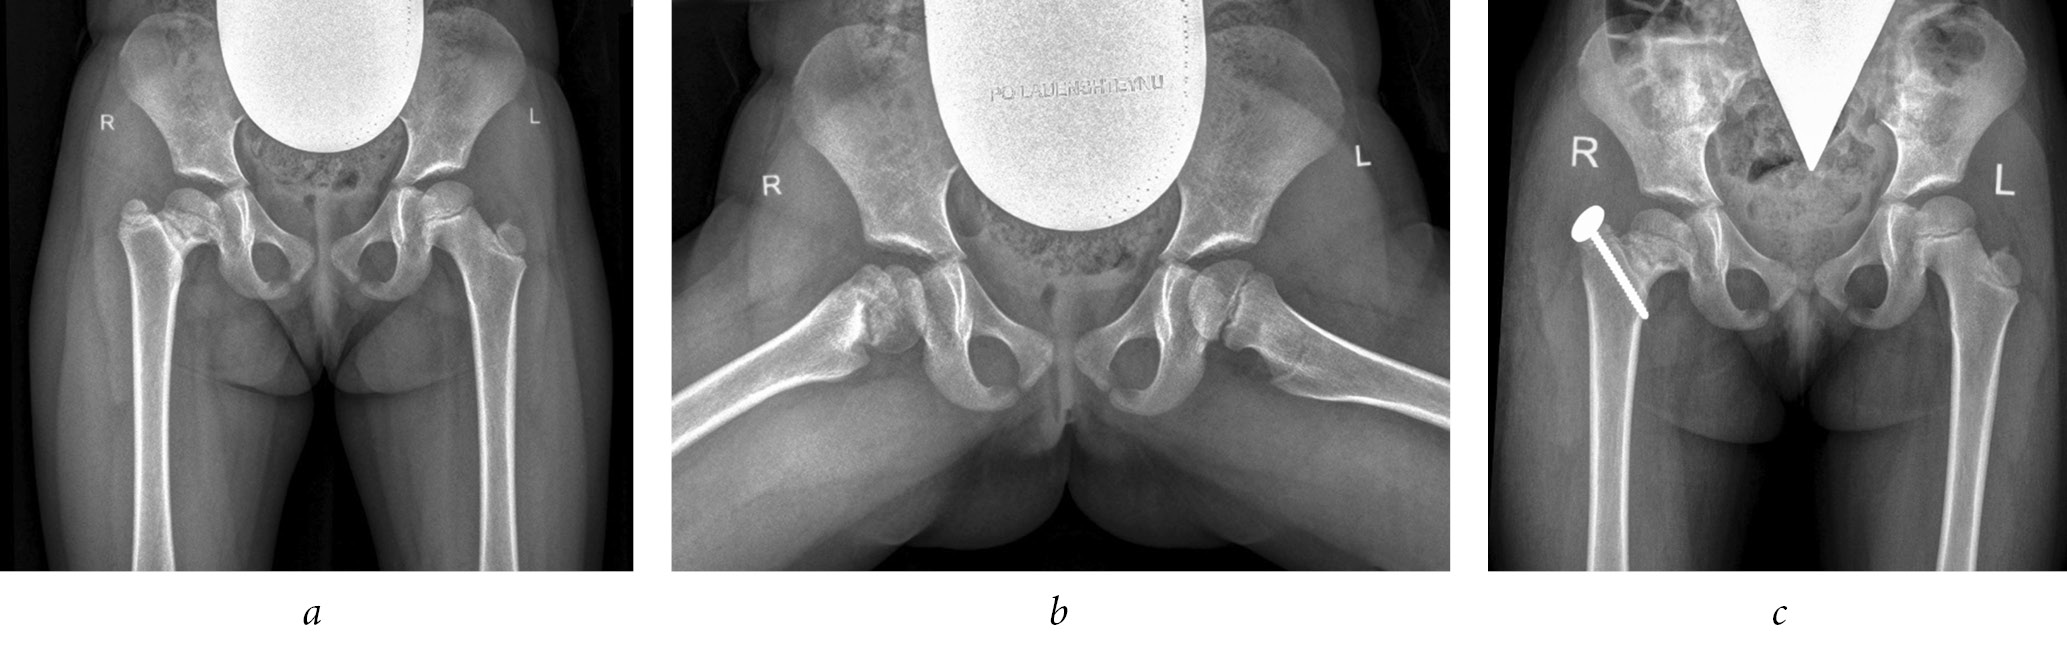

Fig. 2. Radiographs of patient G (4 years old) diagnosed with complications of septic arthritis of the hip joint, emerging high position of the greater trochanter on the right, and multiplanar deformity of the femoral neck with eccentric growth of the epiphysis posteriorly: a, b, before surgery; c, immediately after trochanteric epiphysiodesis on the right

To exclude displacement of the greater trochanter, adherence to bed rest, or use of ambulation support in the postoperative period, before the destruction of the growth zone, the greater trochanter was fixed to the femur using an eight-shaped plate with screws or a cortical screw with a washer. The eight-shaped plate was installed from the lateral surface of the hip, and the cortical screw was inserted from the superior lateral parts of the greater trochanter toward the lesser trochanter parallel to the intertrochanteric line of the femur (Figs. 1, 2) [19].